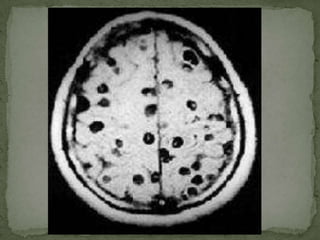

CystercercosisSymptoms depend on location of cysts, but frequently include motor spasms, seizures, confusion, irritability, and personality changeIn the eye, often subretinal or in vitreous.  Movement may be seen by the patient.  Pain, amaurosis, and loss of vision may occur.

CysticercosisClinical manifestationsAdult worms rarely cause sxsLarvae penetrate intestine, enter blood, and eventually encyst in the brain.Cerebral ventircles  hydrocephalusSpinal cord  compression, paraplegiaSubarachnoid space  chronic meningitisCerebral cortex  seizuresCysts may remain asymptomatic for years, and become clinically apparent when larvae dieLarvae may encyst in other organs, but are rarely symptomatic

CysticercosisDiagnosisCT and MRI preferred studiesDiscrete cysts that may enhanceUsually multiple lesionsSingle lesions especially common in cases from IndiaOlder lesions may calcifyCSFLymphs or eos, low glucose, elevated proteinSerologyEspecially in cases with multiple cysts

CysticercosisTreatmentComplex and controversialPraziquantel and albendazole may kill cysts, but death of larvae can increase inflammation, edema and exacerbate sxsWhen possible, surgical resection of symptomatic cyst is preferredCorticosteroids vs. edema and inflammation; antiseizure meds